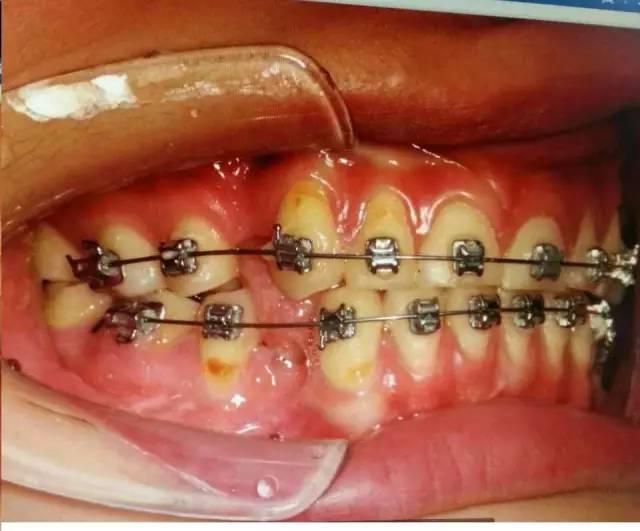

中醫(yī)有云“未病先防”,權(quán)老師發(fā)現(xiàn)患者舌位置的異常,檢查患者的吞咽方式,驗(yàn)證其為嬰兒式吞咽。而舌在嬰兒式吞咽甚至是整個(gè)口頜系統(tǒng)中的作用是不可小覷的。嬰兒式吞咽舌頭抵在下牙,吞咽時(shí)會(huì)對(duì)牙齒產(chǎn)生向外的推力,應(yīng)力集中在頸部,導(dǎo)致牙齒微折裂,甚至出現(xiàn)牙齦萎縮、楔缺、牙根暴露,引起牙的冷熱痛。臨床上會(huì)發(fā)現(xiàn)一些前牙開(牙合)的病人前牙依然受到創(chuàng)傷,沒錯(cuò),依然是舌頭惹的禍。這也可以推測(cè)照片中患者13,43,45牙齦萎縮和頸部楔狀缺損與舌有關(guān)。

患者牙齒出現(xiàn)的癥狀是矯治,側(cè)方干擾,以及舌的推力等因素疊加所致